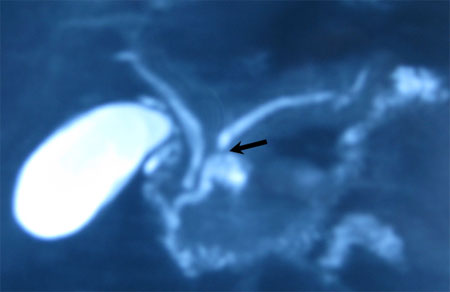

Το IPMN εξορμάται είτε από τον κύριο παγκρεατικό πόρο (η πιο συνηθισμένη μορφή, εντοπίζεται στην κεφαλή του παγκρέατος) είτε από τους πλάγιους παγκρεατικούς πόρους (εντοπίζεται στην αγκιστροειδή απόφυση). Το IPMN του κυρίως παγκρεατικού πόρου έχει μεγαλύτερες πιθανότητες να εμπεριέχει κακοήθεια (εικόνα 1).

Εικόνα 1. Τυπική απεικόνιση IPMN του κυρίως παγκρεατικού πόρου (MRCP). Διακρίνεται το νεόπλασμα (μαύρο βέλος) στην κεφαλή του παγκρέατος.